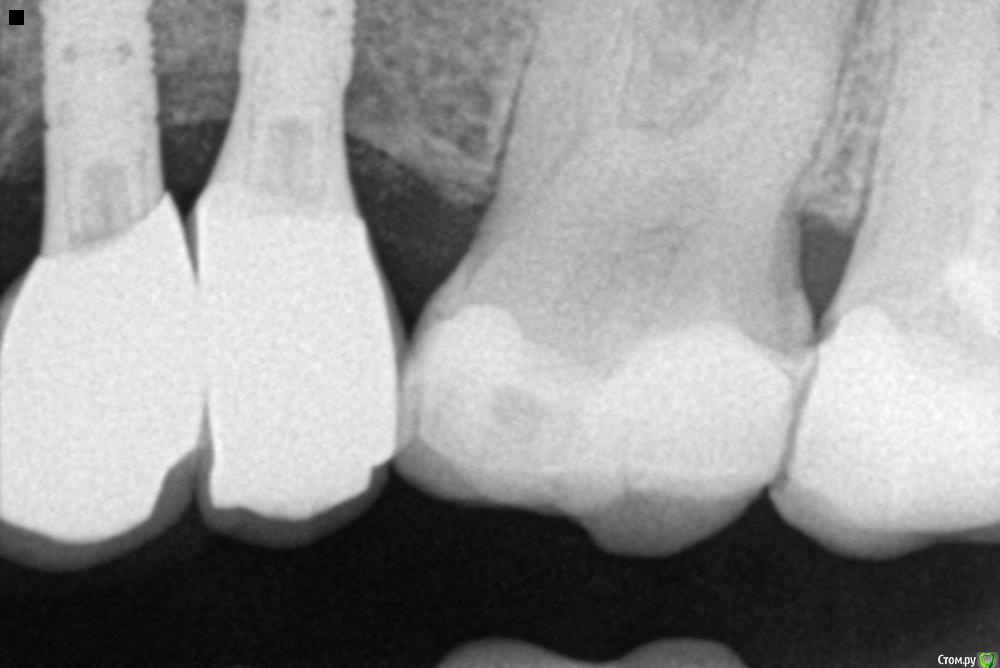

tonkin Опубликовано 5 июня, 2018 Автор Поделиться Опубликовано 5 июня, 2018 Пока такой, проверю, есть ли снимок с глубиной имплантов Ссылка на комментарий

tonkin Опубликовано 6 июня, 2018 Автор Поделиться Опубликовано 6 июня, 2018 Вот еще 2 пано, с наращенной костью до имплантов, и после, когда уже все зажило. Ссылка на комментарий

dok1 Опубликовано 6 июня, 2018 Поделиться Опубликовано 6 июня, 2018 Надо бы срез кт ближнего импланта с клыком. Близковато кажется. А так ничего вроде. Всё по уровню. Ссылка на комментарий

Bier Опубликовано 6 июня, 2018 Поделиться Опубликовано 6 июня, 2018 думаю, что там все ок 1 Ссылка на комментарий